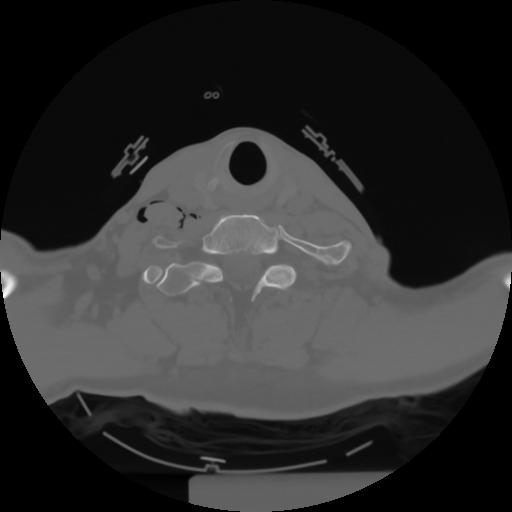

10 P.BLANDAS,,Axial,2.0,P.BLANDAS,,